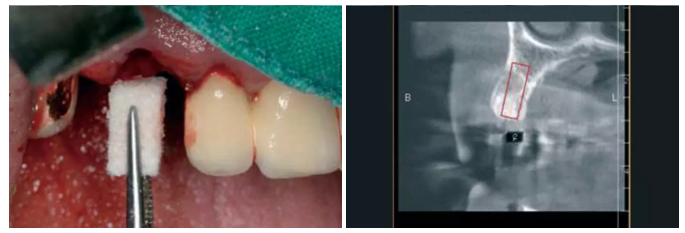

圖10:對Geistlich Bio-Oss® Collagen膠原骨進(jìn)行濕潤(100mg)。 圖11:輕柔的拔除根縱裂的牙齒。

圖12:放置濕潤過的Geistlich Bio-Oss® Collagen膠原骨(100mg)。

圖13:愈合第四個月,種植術(shù)前行錐形束CT檢查。之前植入的Geistlich Bio-Oss® Collagen膠原骨能支撐軟硬組織,避免組織的塌陷,被標(biāo)記了出來。